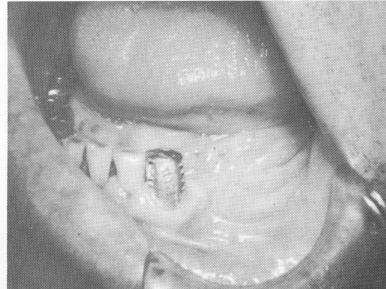

Fig. 11-34. A cuspid casting over tooth preparation.

4 Cuspid casting over mandibular tooth preparation